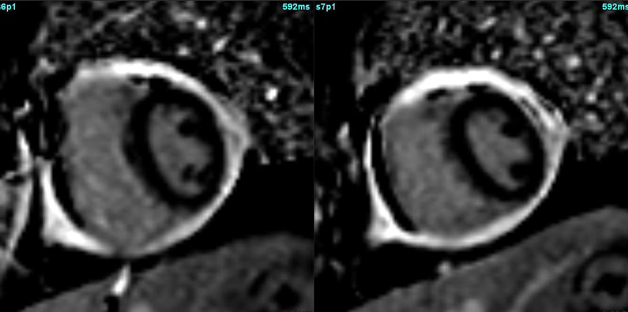

Pericardium

Thick shell around heart!